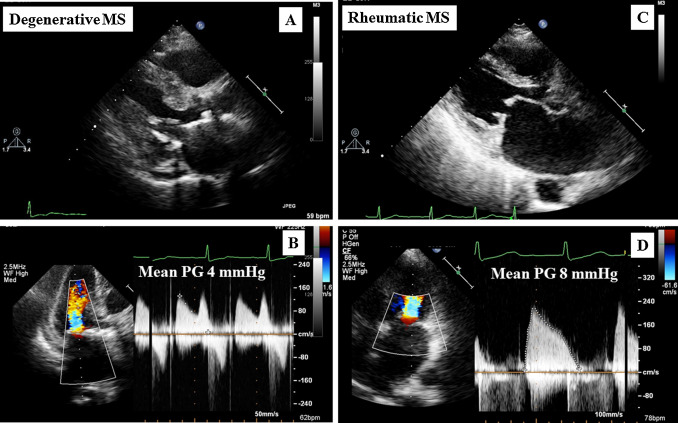

2D ECHO

- Diastolic doming of AMVL creates a hockey stick appearance. MV thickening more than >3mm

- M-mode: decreased EF slope 0-30mm/s, reduced amplitude of E wave, decreased/absent A wave-> CWD Doppler.

- MS severity is usually determined by the pressure half time (p1/2t), MVArea and PG, and PISA – proximal isovelocity Surface Area.

MVA= 220/pressure half-time

Normal 30-60,

Mild 90-150,

Moderate 150-219,

Severe >220

DT Method & MVA: P1/2t = DR x 0.29 and MVA = 759/DT